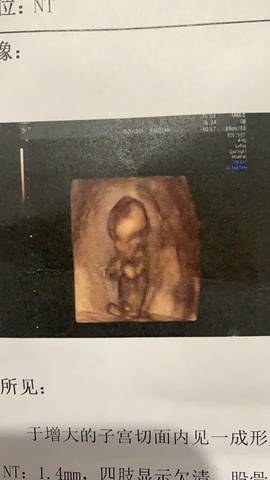

三个月,胎盘位置低怎么解决

journal_insert_pic_1681087008journal_insert_pic_1681087043

#妈妈问答大赛#胎盘低是很容易导致先兆流产的,这段期间一定要注意,不要提重物,而且要多注意休息才可以哦